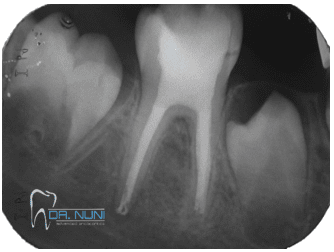

שבר בשורש השן

לעיתים נגרם שבר בשורש השן כתוצאה מהחבלה. מיקום השבר, מידת התזוזה של החלק שנשבר, ומהירות החזרת החלק הנייד וקיבועו הם הגורמים העיקרים שיקבעו את עתיד השן. ככל שהשבר בשורש רחוק יותר מהכותרת (עמוק יותר בעצם) הסיכוי לשמירת השן בפה לטווח הארוך גדול יותר.

שן עם שבר שורש ודלקת